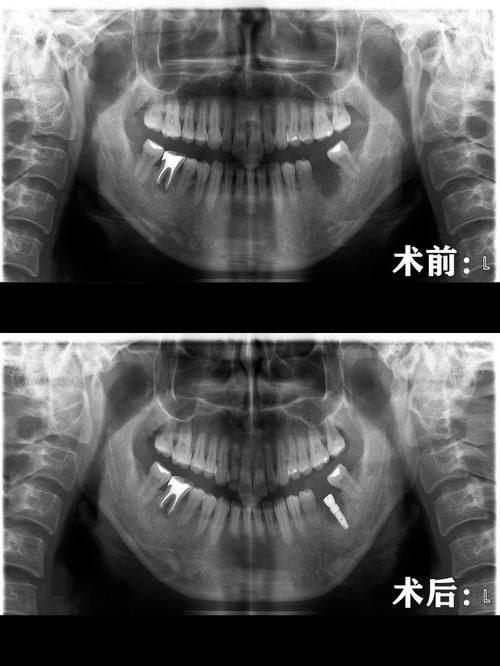

3. 种植牙技术:陈俊龙医生在种植牙方面有着独特的技术优势。他发明的陈氏五合一植牙法结合了多项植牙专项,为患者提供了更效率高、更安心的种植牙解决方案。这种植牙法能够缩短种植时间,提高种植成功几率,让患者更快地修复牙齿功能。同时,他还发明了HSC陈氏水压法鼻窦增高术和VTT陈氏牙龈拉皮法,为种植牙手术提供了更好的基础条件。

1. 创新的技术发明:陈俊龙医生发明了HSC陈氏水压法鼻窦增高术、VTT陈氏牙龈拉皮法和陈氏五合一植牙法等多项技术。这些技术的发明为相关疾病的治疗提供了新的思路和方法。例如,陈氏五合一植牙法结合了多项专项技术,能够提高种植牙的成功几率和效率,减少患者的痛苦和治疗时间。

3. 患者王先生牙齿缺失多年,一直想进行种植牙手术。他了解到陈俊龙医生在种植牙方面有独特的技术,于是找到了陈医生。陈医生根据王先生的口腔情况,采用陈氏五合一植牙法为他进行了种植牙手术。手术非常顺利,术后王先生的牙齿修复了正常的功能。王先生评价说:“陈医生的种植牙技术真的太棒了,手术时间短,成效还好。现在我又可以正常吃东西了,生活质量提高了特别多。陈医生是一位非常值得信赖的医生。”